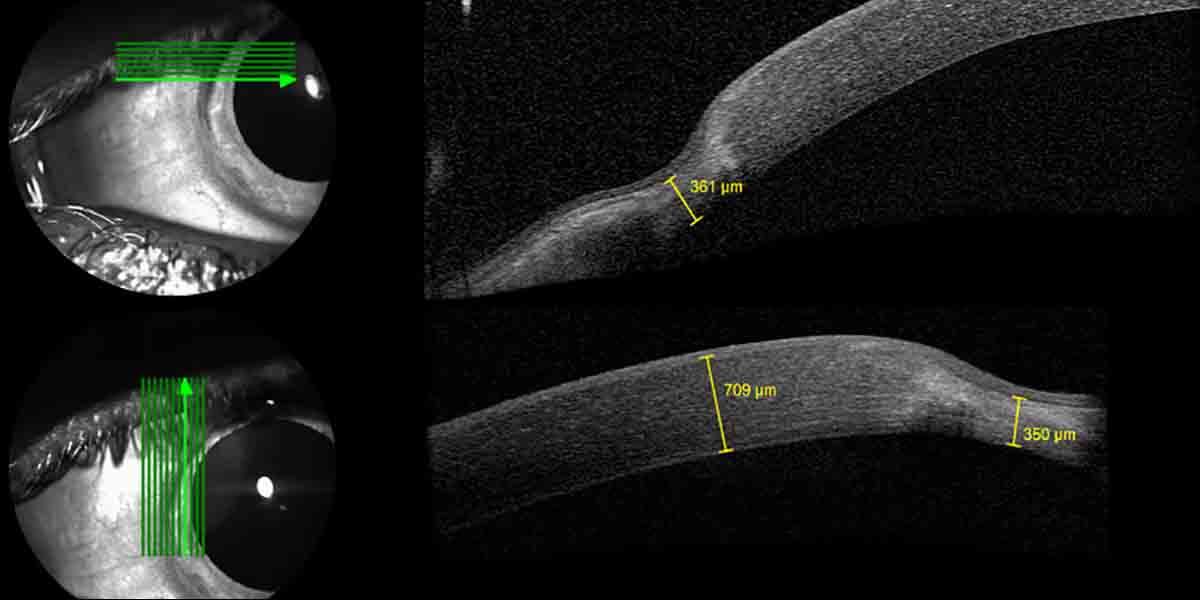

“We only treated two eyes, but it was the first time a Terrien could be stopped and partially reversed,” Farhad Hafezi, MD, PhD, OSN Europe Edition Board Member, said in a telephone interview with Ocular Surgery News